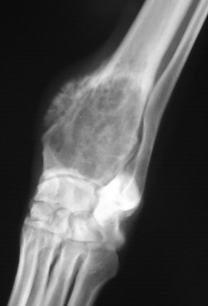

骨 肉腫 初期 症状 骨肉腫の症状・診断・治療・予後 骨・筋肉・関節の病気 All About 10~代の育ちざかりに好発し、21で男性に多く見られます。 発生頻度は稀です。 脛の骨の上端が最もよくできやすい部位です。 いずれもスポーツ障害を起こしやすい.

骨 肉腫 初期 症状 骨肉腫の症状・診断・治療・予後 骨・筋肉・関節の病気 All About 10~代の育ちざかりに好発し、21で男性に多く見られます。 発生頻度は稀です。 脛の骨の上端が最もよくできやすい部位です。 いずれもスポーツ障害を起こしやすい. 子供の初期症状を 骨肉腫 初期症状部位は肩に近い上腕骨に発生しやすい? 骨肉腫に見られる初期症状「すね」 骨の肉腫 希少がんセンター 骨肉腫の初期症状はレントゲンですぐ分かる? 骨肉腫の初期症状は腰に注目せよ!場所や特徴とは?. 骨肉腫について。 骨肉腫は若い人になりやすく10万人に1人がなると聞きました。 症状があるとかそういうわけではないのですが少し不安になってしまったので 初期症状 遺伝するか 主な原因 予防法 生存率 等々詳.

骨肉腫の症状 診断 治療 予後 骨 筋肉 関節の病気 All About